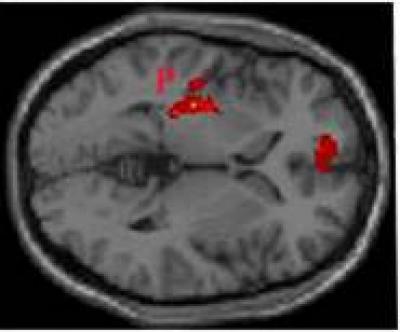

Acupuncture is a traditional Chinese medicine technique that is often used to help improve the level of consciousness in patients with disorder of consciousness (DOC). However, the responses to stimulation of acupoints in patients with DOC are not fully understood. Hao Zhang and colleagues from China Rehabilitation Research Center found that acupuncture at the Yongquan acupoints induced stronger neuronal activity than acupuncture at the sham acupoints shown on positron emission tomography (PET). These researchers believe that acupuncture at the Yongquan acupoints may increase synaptic activity in some areas of the brain. The putamen, cingulate cortex, frontal lobe and cerebellum are involved in conscious thought. This may explain the mechanism by which acupuncture at the Yongquan acupoints results in improvement of patients with DOC. These finding have been published in the Neural Regeneration Research (Vol. 9, No. 5, 2014).

Article: " Neuronal activation by acupuncture at Yongquan (KI1) and sham acupoints in patients with disorder of consciousness: a positron emission tomography study," by Hao Zhang1, Xinting Sun1, Sujuan Liu2, Yingmao Chen3, Feng Ling4 (1 Department of Neurorehabilitation, China Rehabilitation Research Center, Beijing, China; 2 Department of Hyperbaric Oxygen, Fuxing Hospital, Beijing, China; 3 Department of Nuclear Medicine, Chinese PLA General Hospital, Beijing, China; 4 Department of Neurosurgery, Xuanwu Hospital, Capital Medical University, Beijing, China)

Zhang H, Sun XT, Liu SJ, Chen YM, Ling F. Neuronal activation by acupuncture at Yongquan (KI1) and sham acupoints in patients with disorder of consciousness: a positron emission tomography study. Neural Regen Res . 2014;9(5):500-501.